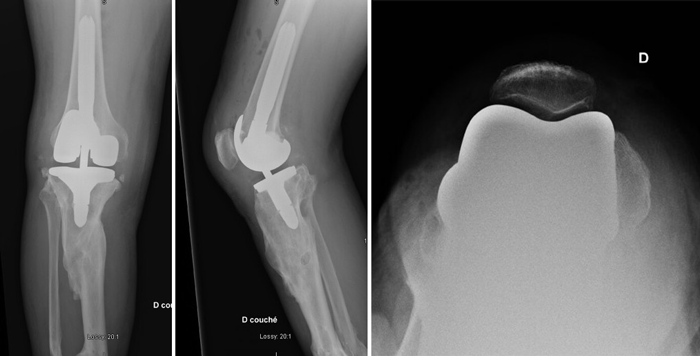

Post-operative X-Rays

Management-of-Total-Knee-Arthroplasty-in-Post-Traumatic-Malunion-figure7

Final strategy decision

A Patient-specific cutting guide on tibial side and a hinged knee prosthesis were used (ADLER ORTHO CUSTOM MADE). Intraoperative tissue sampling was done and an empirical antibiotic therapy was applied before the bacteriological samples came back negative.